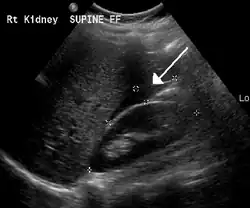

The use of ultrasound has become the standard of care when preparing a patient for paracentesis. Confirmation of an ascitic effusion reduces the risks associated with a dry or blind tap of the abdomen. Anatomic landmarks, such as the midline linea alba approach, were traditionally used as reference points for needle insertion. Phased array or curvilinear ultrasound transducers are typically used in the hospital and outpatient setting to identify ascites in the abdominal cavity. Fluid within the abdominal cavity appears hypoechoic or anechoic (black) on ultrasound. Morison's pouch (hepatorenal recess) is a common starting location in concordance with ultrasound FAST (focused assessment with sonography for trauma) exam. Fluid collection can occur in a number of different locations and may be difficult to find, especially if the patient only exhibits a small volume of ascites. Measurement of the amount of fluid within the abdominal cavity is not necessary or very successful. Identification of sufficient fluid within the abdominal cavity for fluid analysis or to achieve a therapeutic benefit is all that is required to proceed to paracentesis. Ultrasound guidance of the paracentesis can also be used as an additional safety measure to ensure the needle stays within the ascitic fluid and avoidance of important vessels within the abdominal cavity.[5]

Small fluid collection in Morison's pouch